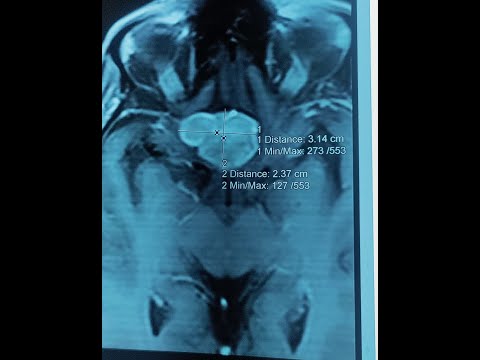

Hellow guys, Welcome to my website, and you are watching D11 D12 NEUROFIBROMA-DR LAXMIKANT BHOPLE/DR SANDEEP GORE SHREE GANGA HOSPITAL NANDED. and this vIdeo is uploaded by Dr. Laxmikant Bhople NeuroCare at 2024-07-24T04:56:42-07:00. We are pramote this video only for entertainment and educational perpose only. So, I hop you like our website.